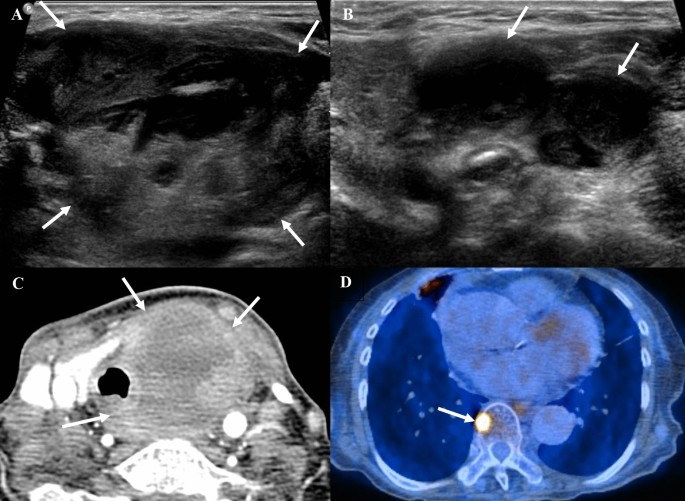

When comparing US features based on survival period, nodules in patients with a survival period of less than 12 months were larger (5.17 ± 1.49 cm vs. 3.95 ± 1.63 cm, p = 0.005) and more likely to be suspicious for gross ETE on US (91.43% vs. 69.57%, p = 0.04) (Table 2, Fig. 3 and Fig. 4). Other US features, such as composition, echogenicity, margin, orientation, echogenic foci, heterogeneity, lobulation, K-TIRADS, and ACR TI-RADS, did not significantly differ between the two groups (p > 0.05).

A 78-year-old woman diagnosed with anaplastic thyroid carcinoma, confirmed to be negative for TERT promoter mutation. (A) The transverse US image displays a 5.9 cm lobulated, predominantly solid, markedly hypoechoic nodule in the left thyroid gland, exhibiting parallel orientation and suspicious gross extrathyroidal extension (ETE) (arrows). (B) Multiple suspicious cystic metastatic lymph nodes are evident in both bilateral necks (arrows). (C) The axial contrast-enhanced CT image reveals a large necrotic mass in the left thyroid gland that is heterogeneously enhancing, with gross ETE and direct invasion of the adjacent trachea, esophagus, and anterior strap muscle (arrows). (D) The PET-CT image illustrates uptake in the thoracic spine (arrow), suggestive of bone metastasis. The patient died 1.57 months following diagnosis. CT, computed tomography; PET-CT, positron emission tomography-computed tomography; TERT, telomerase reverse transcriptase; US, ultrasonography.